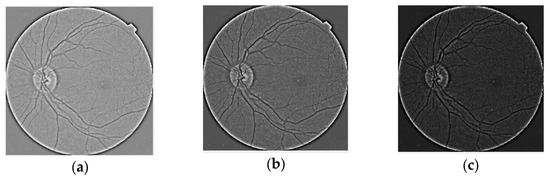

- We designed adjustment parameters by contrast as gamma correction and creating new image sets for each DR level.

- Images were processed before manipulating contrast.